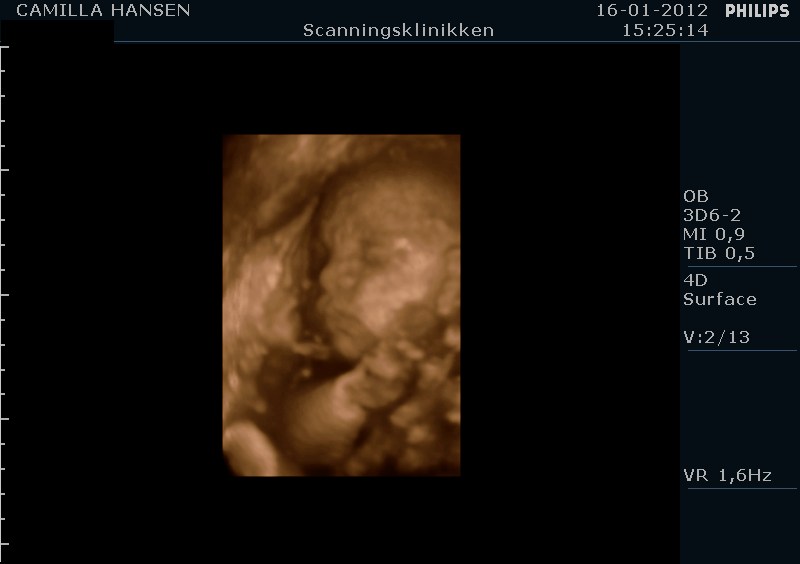

babymus77 skriver:

Ejj hvor er de gode og tydelige 3D billederne:-) Jeg skal her d 20 april, men ved ikk om det er for tidlig?? Er der 26+3???

tak det er nogle rigtige gode billeder.....

jeg var i uge 28 eller 29 og det må helst ikke være sener ind det.

jeg fødte d.26/3 2012 og billederne passer hun ser ud som på billederne.

3d/4d scanninger er helt klart noget jeg vil anbefale.